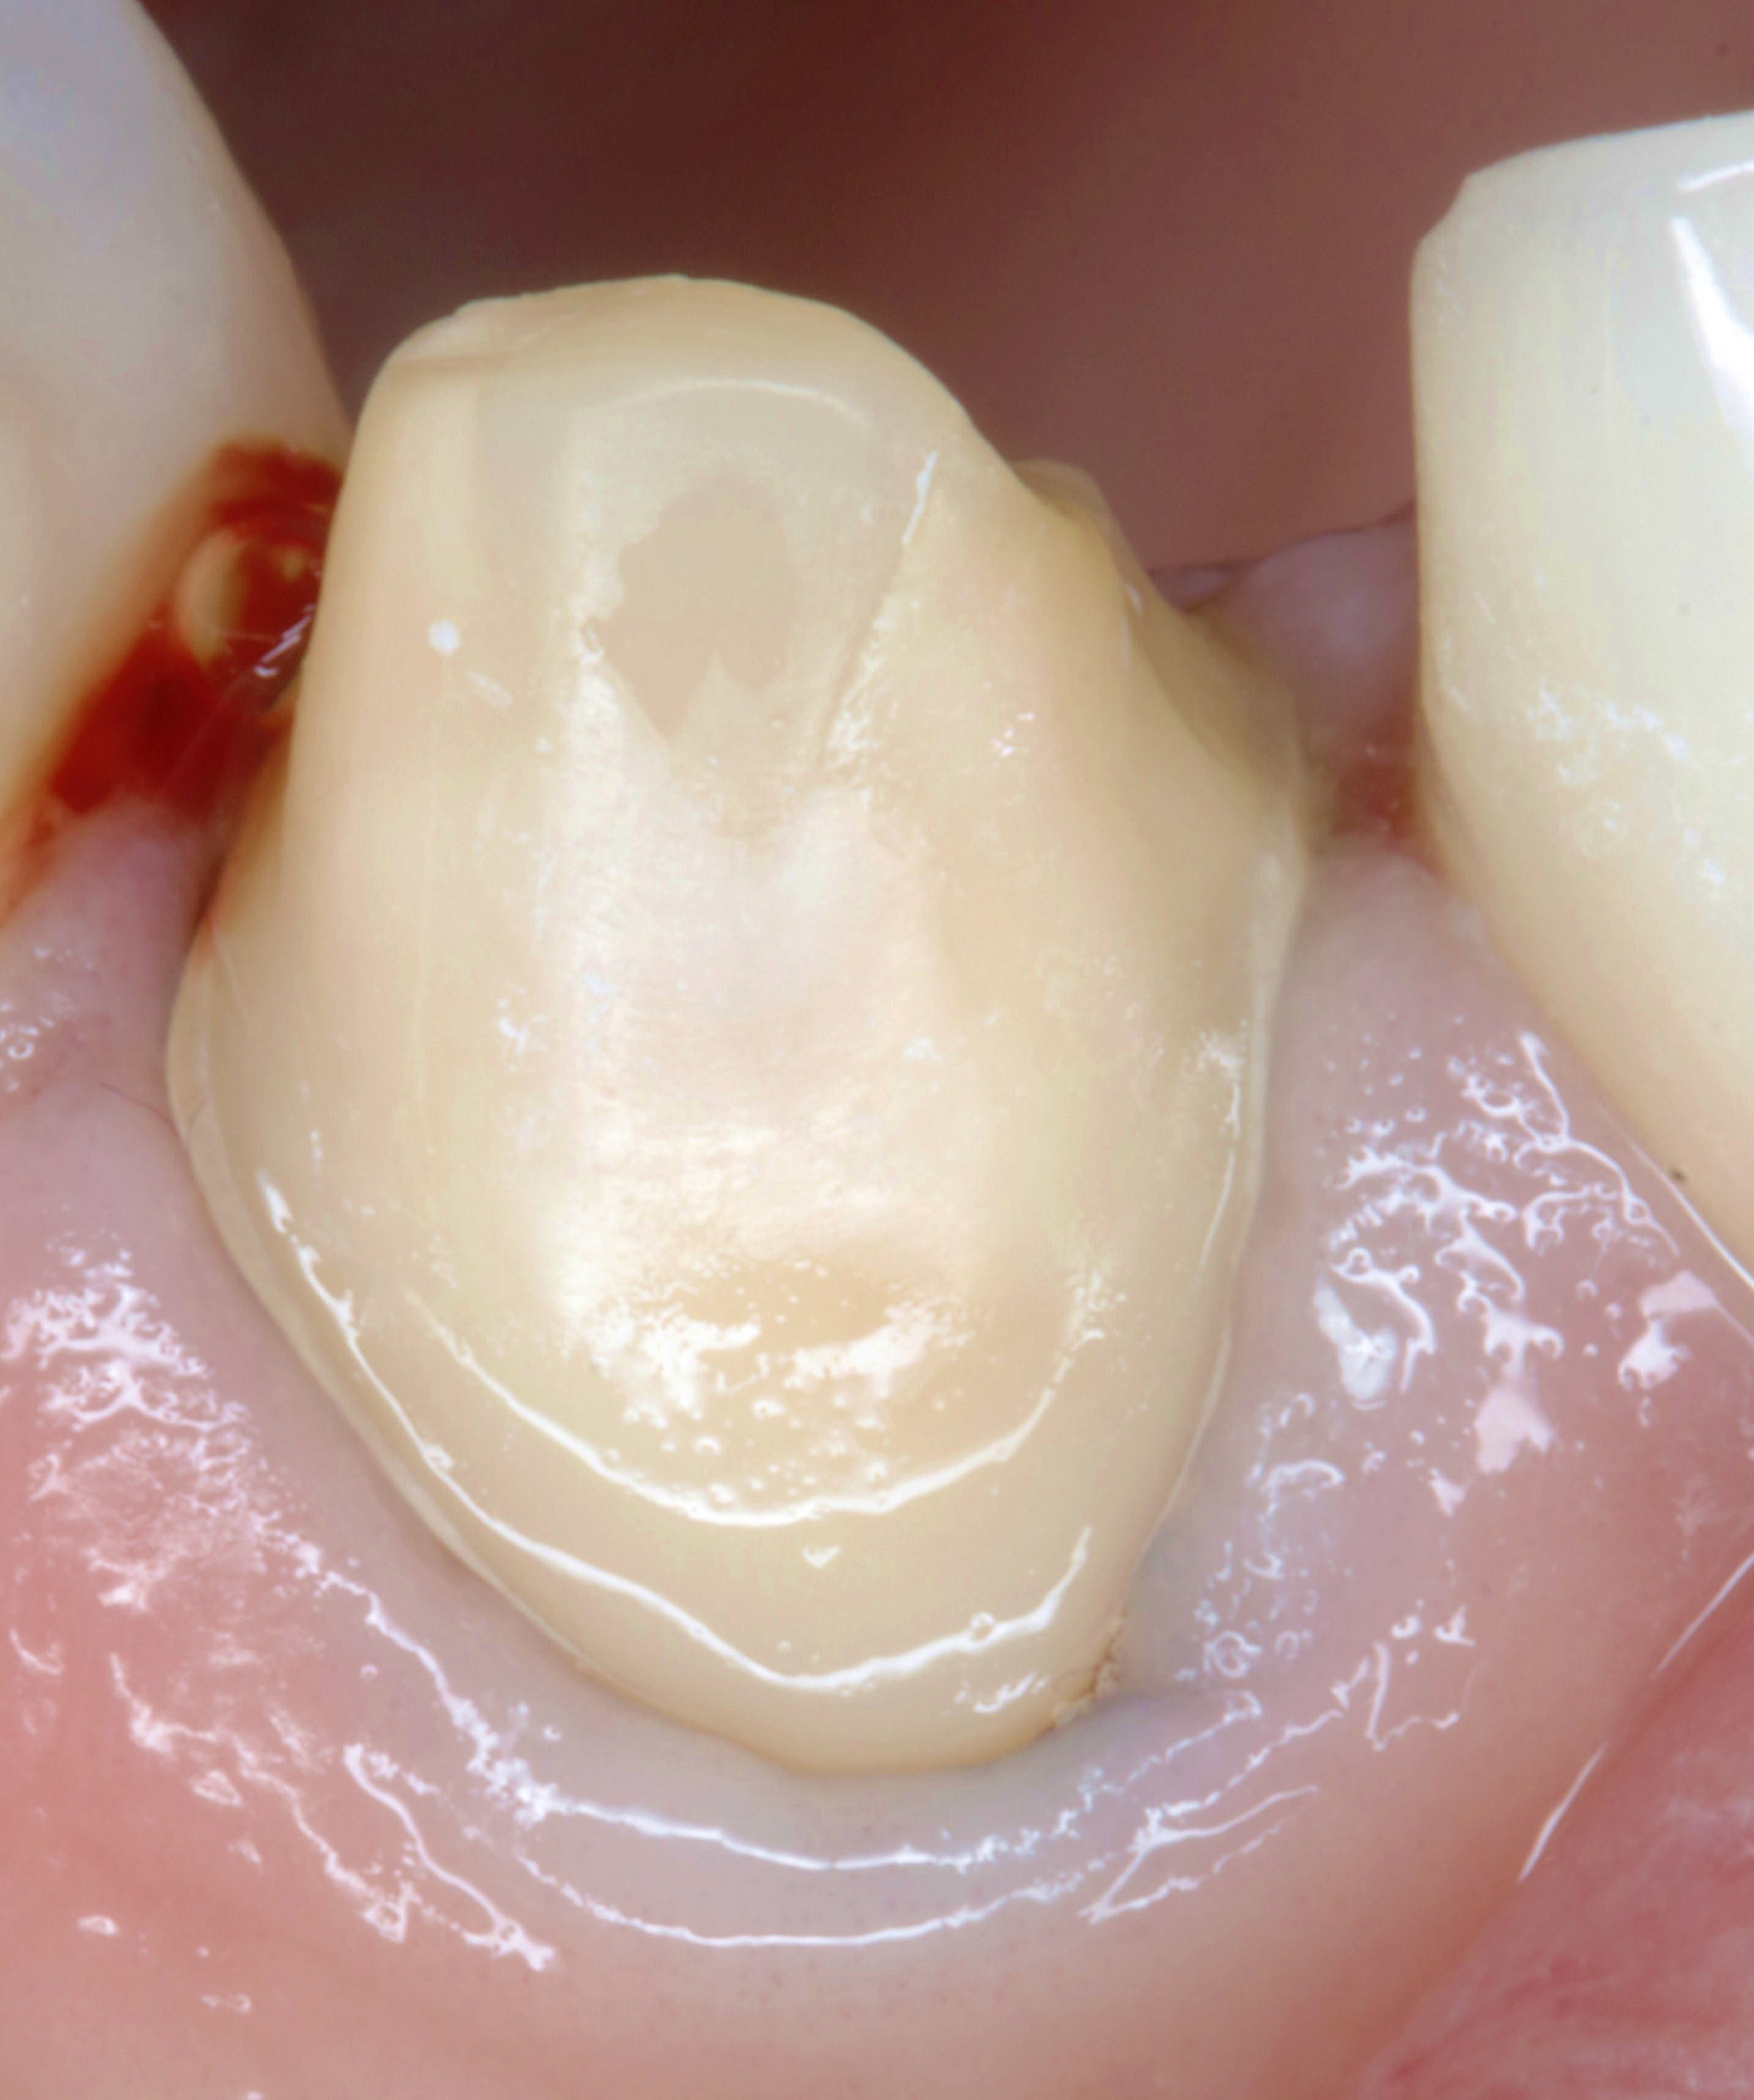

regarde c'est du gros moignon , Ca tiendra sans problème ... même en scellant si je veux

De de toute façon c'est une ancienne suceuse avec proalveolie . Même En propulsion elle ne les touche pas ses incisives

J'avais même pas besoin d'une empreinte antagoniste pour les faire puisqu'il y a pas de contact incisif

Lardonbis , tjs suite a ta question sur les limites mais en photo ,

voilà la taille de la page 25 , 1 semaine apres .

pourtant ,lors de la taille il n'y avait pas de fil , et la gencive pas trop touchée .

eh bien ,les limites apparaissent naturellement .

et donc avant de prendre l'empreinte , autant reprendre les limites ,et ç est là qu'intervient le fil .

et la taille du fil depend de la profondeur où tu veux placer ta limite . voilà pourquoi il y a plusieurs tailles :-).

et quand tu le mets il n'y a pas une goute de sang .

( là ça saigne pcq j'ai fait le compo mesial de 24 )

et donc apres finition des limites ça donne ça , et comme ça ne saigne pas ,on peut prendre l'empreinte .

et là la gencive sera stable ,comme sur la 22 ou j'ai posé une àmax il y a quelques années .